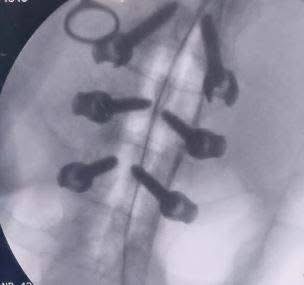

استمر الفريق في تحقيق إنجازاته، حيث أجرى جراحة دقيقة لمريض يعاني من خذل نصفي بسبب ورم بالفقرات الصدرية، مما أدى إلى تحسن حالته فورًا. كما نجح في استئصال ورم بالمخ لسيدة تبلغ من العمر 51 عامًا باستخدام الميكروسكوب الجراحي.